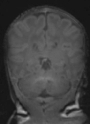

For the preterm infant, the provision of diagnostic measurements of brain compromise is a high priority, in order to minimise the risk of developmental impairment. Amplitude-integrated electroencephalography (aEEG) is used to monitor the functional status of the brain and to observe maturational changes during extrauterine development. Near-infrared spectroscopy (NIRS) enables continuous estimation of cerebral oxygenation. General movements (GM) are part of the spontaneous movement repertoire of newborn infants. The presence, quality and intensity of GM are markers of central nervous system integrity. Quality of GM has emerged as a reliable predictor of neurodevelopmental delay in preterm infants. Cerebral magnetic resonance imaging (MRI), performed at term-equivalent age in all very preterm infants, provides detailed information on the wide spectrum of preterm brain injury and alterations in postnatal brain development in preterm infants (Fig. 1).

Our research laboratory focuses on the evaluation of potential neuroprotective drugs in different in vivo and in vitro models to counteract newborn brain injury (Fig. 2). One current focus is on evaluation of the therapeutic potential of endogenous sigma-1 receptor ligands, such as dehydroepiandrosterone and its sulphate ester, and of levomepromazine, a phenothiazine neuroleptic drug with strong analgesic and sedative properties.